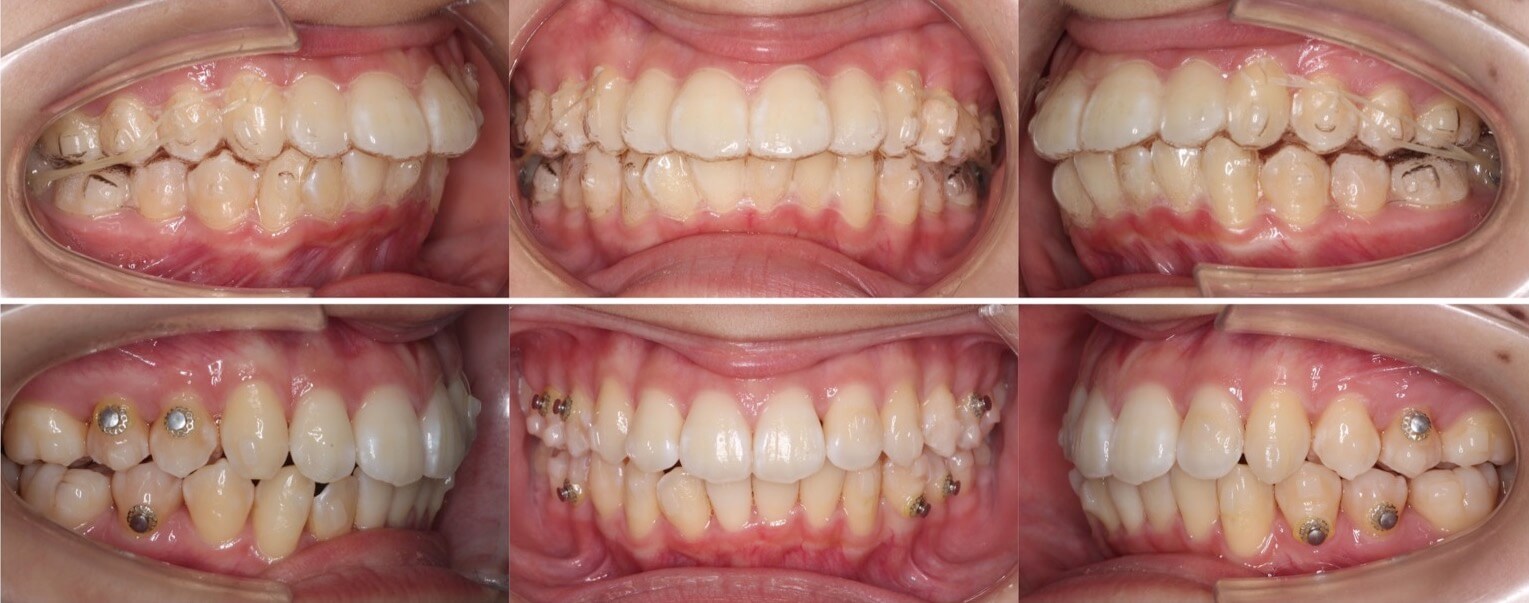

高校生女性・唇側矯正装置・上抜歯

上の前歯が前に出ているため下唇に当たり口が閉じづらいという症状を、抜歯を併用して前歯を引っ込めて治しました。術後は奥歯を含めて理想的なかみ合わせになり、スマイルも大きく変化しました。ご本人からも大変満足していただけました。少し前歯が小さめですが、唇側矯正装置であればしっかりと歯の動きをコントロールする事ができます。

<症例概要> 難易度★★★☆☆

主訴:出っ歯

年齢・性別:高校生女性

住まい:千葉県船橋市

症状:上顎前突・叢生・過蓋咬合・右側シザースバイト

治療方針:上抜歯空隙閉鎖(中等度固定)・ストリッピング

治療装置:唇側矯正装置

固定装置:ナンスホールディングアーチ

抜歯:上第一小臼歯(計2本)

治療期間:2年2か月

リテーナー:上プレートタイプ+クリアタイプ・下フィックスタイプ

治療費用:968,000(税込)

代表的副作用:痛み・治療後の後戻り・歯根吸収・歯髄壊死・歯肉退縮